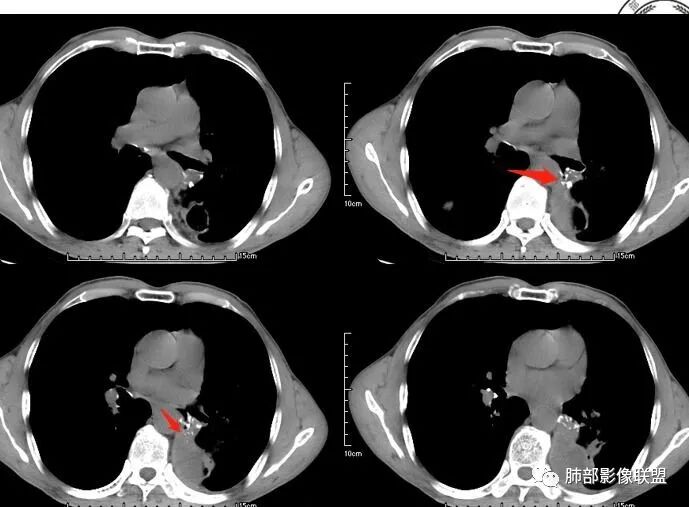

空洞型肺转移瘤成因尚不完全明确, 可能与鳞癌中心角化物排空 、腺癌黏液样退变后黏液排空 、肿瘤血供不足引起坏死 、肿瘤继发脓肿 、化疗等机制有关,其中部分薄壁囊腔样结可能是肿瘤细胞沿着原有的肺大泡或其它囊性结构生长或者肿瘤向小支气管侵犯引起活瓣性阻塞而形成 ,但无一种机制能解释全部现象。空洞或囊腔大小并不反映病情变化, 其临床意义不大, 而瘤灶的数目及大小, 特别是瘤灶实性成分的多少才可能更准确反映病情变化。肺癌形成空洞与其肿瘤本身性质有明显联系,肿瘤分化程度差,倍增时间越短,恶性程度越高,组织液化坏死形成空洞倾向越明显;鳞癌空洞偏大,内缘不规则,常易形成X线平片中癌梁样改变与CT中壁结节样改变;而腺癌空洞大小不定,洞内分隔明显,内缘不规则,且较难于形成壁结节等改变;合伴空洞的肿瘤边缘情况也对判断肿瘤性质有帮助。

其中囊样空洞和小环形空洞属于薄壁空洞,泡样空洞和不规则空洞属于厚壁空洞,其中腺癌空洞型肺转移瘤主要表现为小环形空洞,以下3个病例均表现为小环形空洞的转移瘤:

本病例左肺下叶肿块,有深分叶、毛刺、胸膜牵拉凹陷、支气管截断及纵隔内淋巴结肿大等征象,都均支持病灶为恶性,如腺癌,而且叶间裂的多发结节也提示是腺癌来源可能大;双肺多发结节、肿块,大部分病灶有分叶、毛刺及胸膜凹陷的恶性征象,与原发肿瘤本身的性质有关,所以应该与左肺下叶肿块同源,而且双肺多发病灶内空洞也具有多样性;

此病例中空洞形态多样,内壁不光整,有分隔影,周围未见明显卫星灶及钙化灶,结核不太符合;患者病史慢性病史,无明显发热,缺乏中毒临床表现,急性感染基本排除;各种中性粒细胞胞浆抗体阴性,没有鼻窦炎,肾脏等病史,基本排除血管炎;霉菌性空洞常见于免疫机能低下者, 常为空洞、肺炎、伴“ 晕圈”征的结节及支气管扩张合并存在。